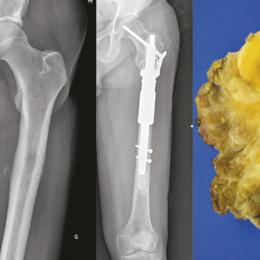

Sarcomes

Les sarcomes désignent des cancers des tissus conjonctifs. Ce sont des tumeurs rares et hétérogènes qui affectent environ 6 000 individus par an en France. Plus de 150 sous-types sont répertoriés dans la dernière classification de l’Organisation mondiale de la santé. La…